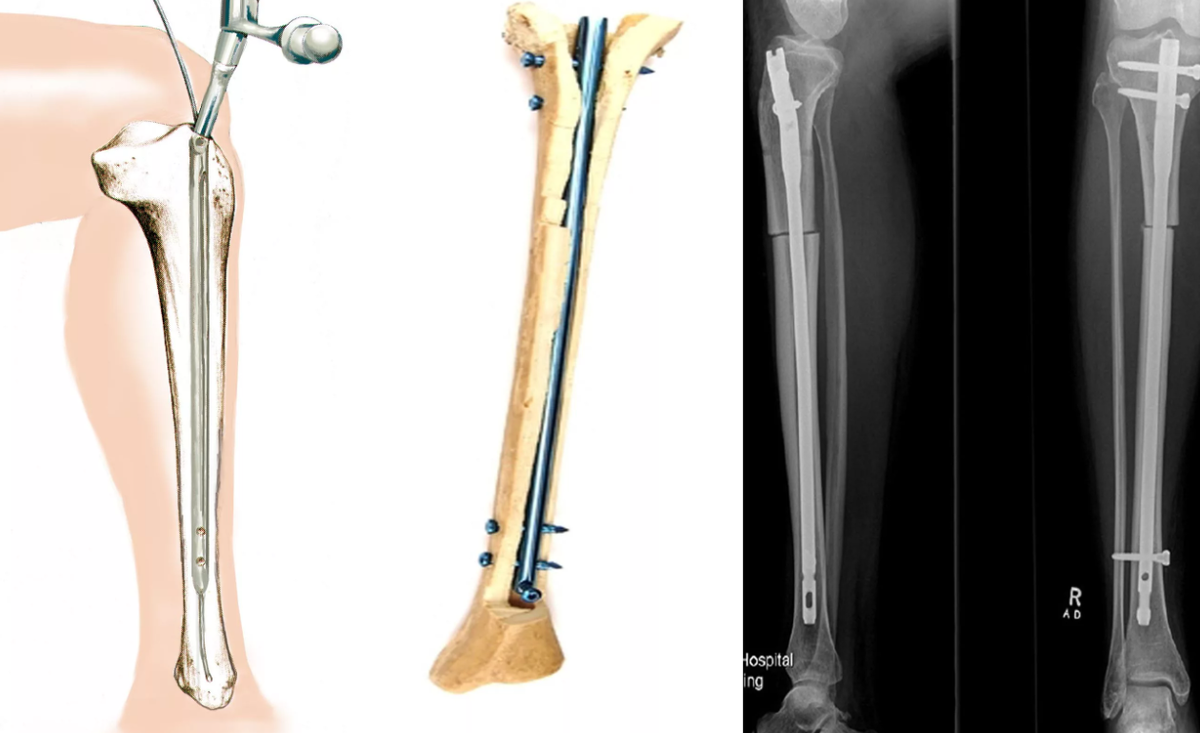

• погружной остеосинтез стержнями – это достаточно сложная операция, которая предполагает, что накостный остеосинтез в виде пластин вводится непосредственно в область, где сформирован перелом. Конструктивное устройство определяется в соответствии с особенностями перелома. В данной ситуации используется накостный, чрезкостный и внутрикостный способ введения специальных пластин. Хирургический тип остеосинтеза имеет свои преимущества и недостатки. Прежде, чем принимать решение об осуществлении процедуры, назначается детальная диагностика.

Самым простым вариантом считается накостный остеосинтез. Речь идет о том, что фиксатор перелома будет закрепляться над костью, соответственно, уровень травматизма хоть и будет достаточно высоким, но практика показывает, что период реабилитации также не является слишком длительным. Соответственно, накостный остеосинтез назначается достаточно часто. Внутрикостный остеосинтез – операция, которая требует введения фиксатора непосредственно в кость. Такой процесс является более травматическим, используется исключительно в сложных ситуациях. Период реабилитации будет более значительным, обязательно включает в себя период физиотерапевтических процедур для более интенсивного заживления. То есть, внутрикостный остеосинтез имеет серьезные основания и является более сложной процедурой.

Чрезкостный метод остеосинтеза также используют в сложных ситуациях. Каждый метод остеосинтеза имеет свои определенные особенности, а значит, выполняться должен опытным специалистом своего дела. Не менее важным является детальный и высококачественный процесс диагностики, на основании которого можно будет правильно принять решение об используемом методе, также о том, какие могут быть побочные осложнения.